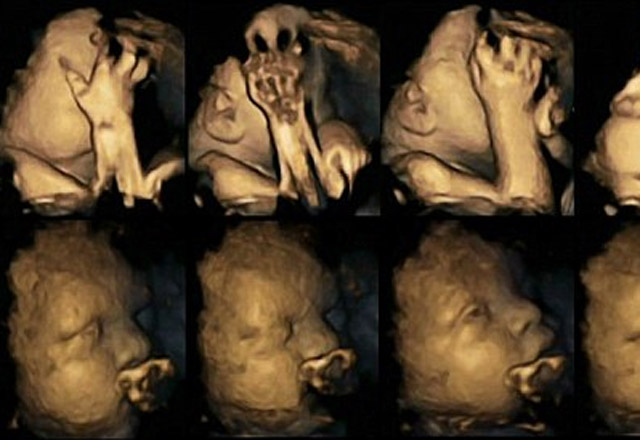

Daily Mail'de yayınlanan bir araştırmada sigara içen ve içmeyen annelerin bebeklerinin 4D ultrason görüntüleri yayınlandı.

İngiltere'de yapılan bir araştırma sigaranın anne karnındaki bebeklere bile ne kadar zarar verdiğini ortaya koydu. 4 boyutlu çekilen fotoğraflarda anne sigara içtiği zaman bebek ağzına ve yüzüne dokunuyor. Bu oran, annesi sigara içmeyen bebeklerden kat be kat daha fazla. Bu taramalar açıkça bize gebelik sırasında annenin sigara içmesinin bebeğe ne kadar zarar verdiğini ortaya koymaktadır.

Fetüsler normalde kendi ağızlarına ve yüzlerine doğum öncesi daha az dokunuyor. Sigara ayrıca bebeklerin sinir sisteminin gelişmesini de yavaşlatıyor. Araştırmacılar, bu fotoğraflardan sonra hamile annelerin sigara içmeyi bırakacaklarını umuyor.

Durham Üniversitesinde yapılan araştırmada yer alan Dr. Nadja Reissland, araştırma için 20'ye yakın anne adayının gözlemlediklerini söyledi. Bu kişilerden dördünün günde 14 sigara içtiğini kaydeden Reissland, "Görüntülerdeki bebekler 24, 28, 32 ve 36 haftalık. Tiryaki anneler erken doğum riskiyle karşı karşıya. Bebekleri solunum rahatsızlığıyla karşı karşıya kalabilir, kandaki bir pıhtı yüzünden hayatını kaybedebilir" dedi. Yapılan araştırmalara göre İngiltere'deki hamile kadınların yüzde 12'si sigara içmeye devam ediyor, bu oran Orta Doğu'da ise yüzde 20 civarında. Araştırma sonuçları Acta Paediatrica dergisinde yayınlandı.